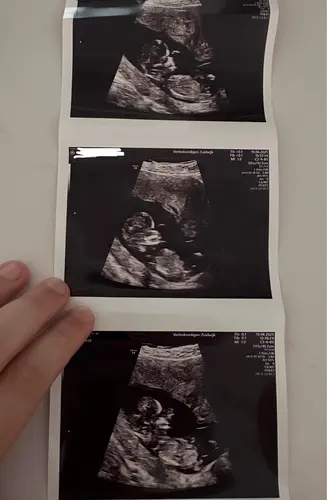

Iemand hier een idee wat het kan zijn☺️